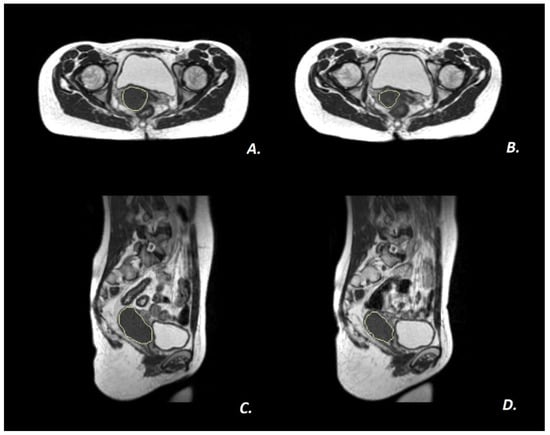

2.2. MRI Imaging Protocol and ERITCP Definition

2.3. ERITCP Definition and Performance Evaluation